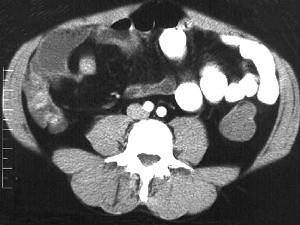

问题 女,30岁,右下腹痛,腹泻便秘交替出现,消瘦乏力,血沉加快,X线检查如图,最佳的诊断是 ( )

选项 A、结肠癌 B、阑尾炎 C、小肠结核 D、小肠克罗恩病 E、小肠癌

答案 D